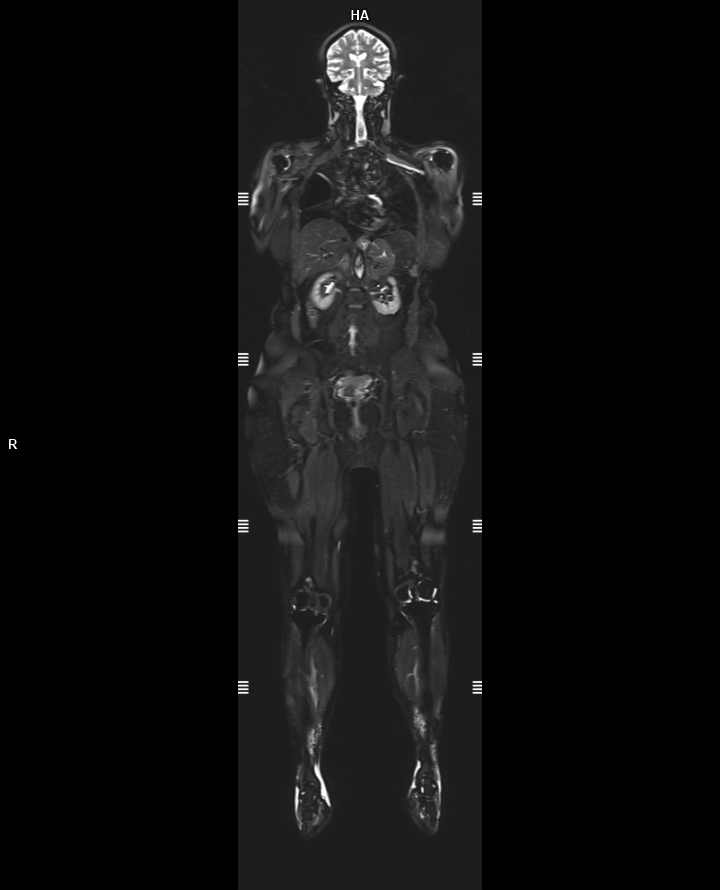

• 3 TESLA MR ÇEKİM GÖRÜNTÜLERİ

3 Tesla MR Çekim Görüntüleri

• 3 Tesla MR Çekim Görüntüleri